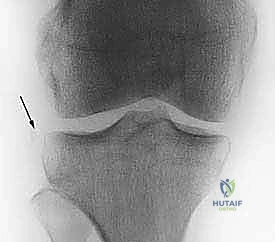

- الأشعة السينية (X-rays): تُطلب أولاً لنفي وجود أي كسور عظمية مصاحبة، مثل كسر "سيجوند" (Segond Fracture) وهو كسر قلعي صغير في الجانب الخارجي للقصبة يُعتبر علامة شبه مؤكدة لتمزق الرباط الصليبي.